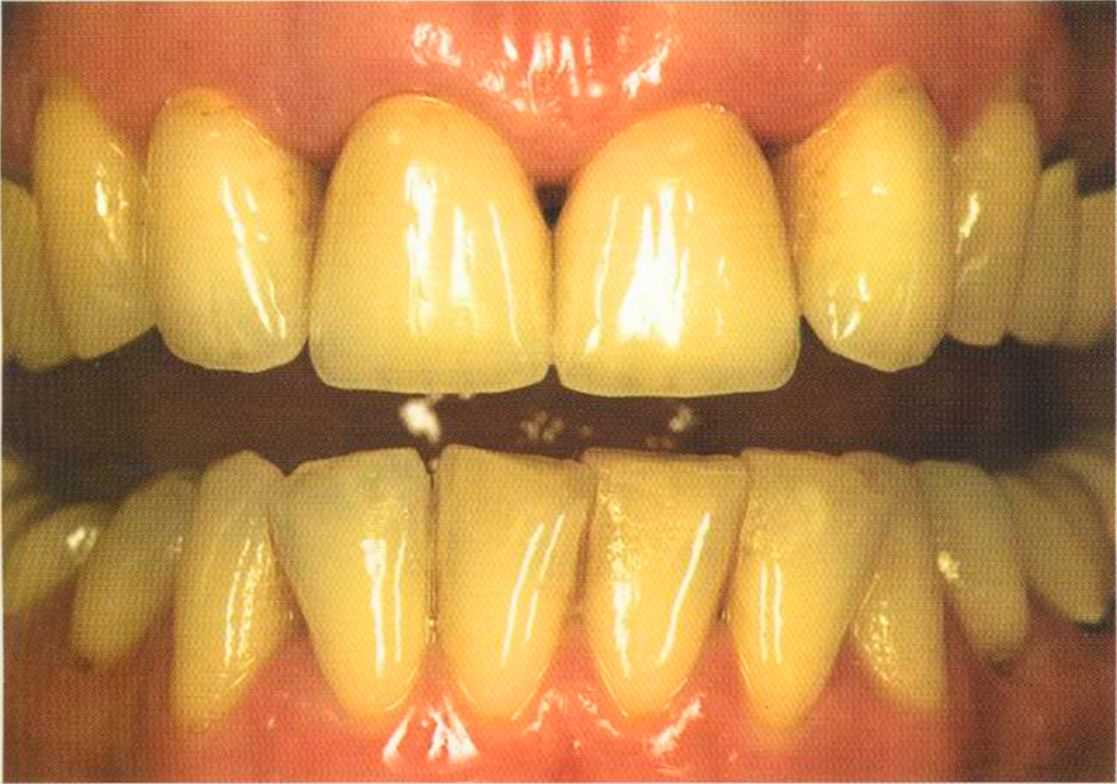

Только что зацементированные коронки. До сих пор сохранилось воспаление десневого сосочка. Уже через несколько дней он будет здоровым, бледно-розового цвета.

Первое лечение проходию много лет назад у другого доктора. Со временем ос те пи / ка уху дин ьась, особенно в пришеечной области. Этот пациент хотел новые коронки в области 12 и 22, по сомневсься, нас кол ько хорошо они будут выглядеть.